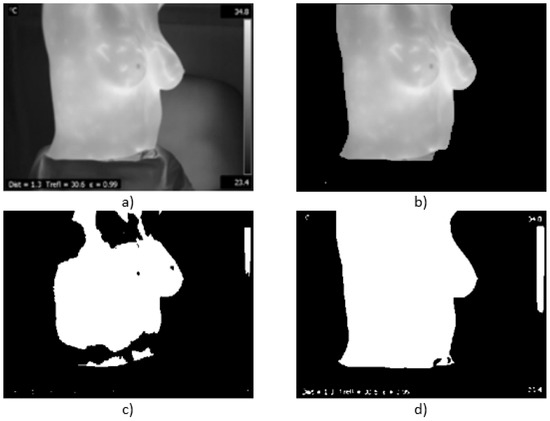

- Case 2, healthy,In Figure 17, the proposed methodology is applied to a woman with a thin constitution. In the acquired thermogram shown in Figure 17a, it is possible to see how a small region corresponding to the seat was segmented together with the patient body by Otsu’s method; however, this does not mean any problem for the finding of inferior limits exhibited in Figure 17a–d. Although at this time, the armpit slope is lighter than the previous case, the proposed segmentation results in being robust enough to separate the right and left breast zones, as can be seen in Figure 17e,f.Finally, the average temperatures present in the right and left breast side are shown in Table 5. Again, the difference of temperatures is less than 1 °C, with a result of no problem detected. This time, the difference between the maximum values is greater than 2 °C and could be associated with the segmentation result shown in Figure 17e, which also includes the side of the breast.